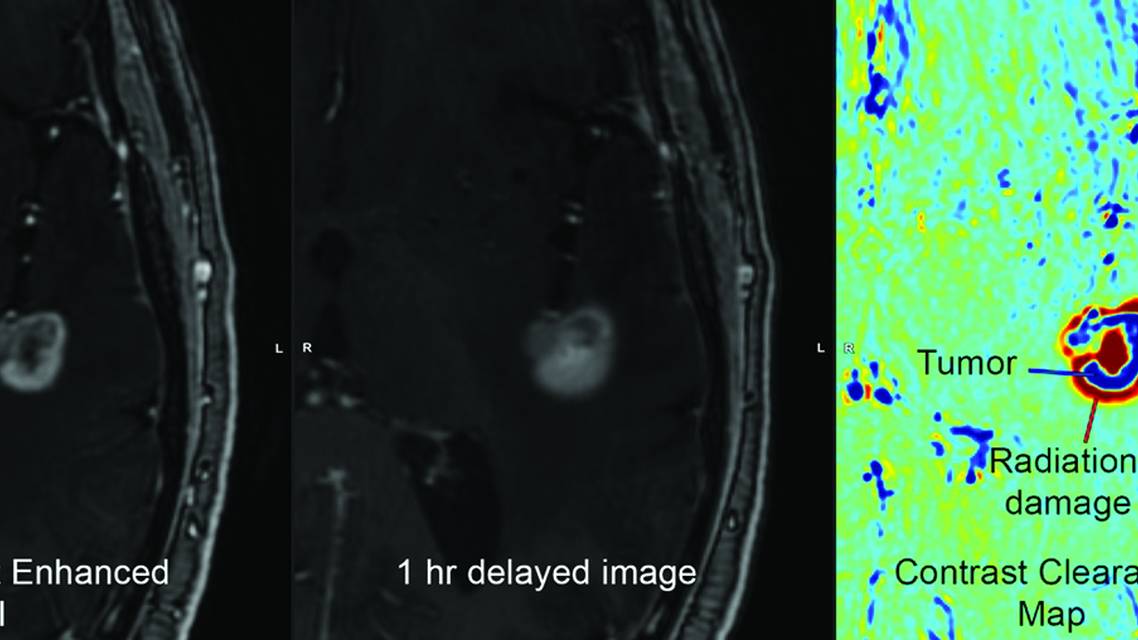

Conventional MRI scans often cannot be used to resolve the ambiguity between recurrence and radiation effect. CCA MRI has emerged as a powerful tool in this situation. CCA (also called delayed contrast enhancement MRI or treatment response assessment maps) involves acquiring early and late (often 1-hour postcontrast) T1-weighted sequences and automatically subtracting them. Contrast washes out from viable tumor, whereas it accumulates in brain exhibiting treatment-induced adverse effects or necrosis.23 The resulting map highlights areas of accumulating contrast (color-coded red) and areas of contrast washout that correlate with active tumor (color-coded blue, Figure 1).

Figure 1. Contrast clearance map shows a combination of residual tumor and radiation effects on a brain metastasis treated with 20-Gy Gamma Knife radiosurgery 6 months previously, allowing decisions regarding response, retreatment, and symptom management. CCA images are color coded to show tumor and vasculature in blue and radiation effects in red.

CCA has shown excellent diagnostic performance. In one prospective series of 32 treated lesions, CCA correctly differentiated radiation necrosis or pseudoprogression from true progression with 93% sensitivity and 78% specificity (overall accuracy 84%).15 A recent systematic review of 9 studies (407 lesions) found a pooled CCA sensitivity of 91% and specificity of 92%.24 These figures exceed those of standard MRI sequences and compare favorably with perfusion and spectroscopy. Histologic studies have validated CCA results: in mixed cohorts of gliomas, metastases, and atypical meningiomas, delayed enhancement patterns on CCA correlated with pathology in 100% of cases.23 In practical terms, CCA is relatively easy to implement on modern scanners (ie, acquiring a second T1 sequence ≥60 minutes postcontrast) and can quickly produce heat maps of tumor activity without the need to use any radioactive isotopes.